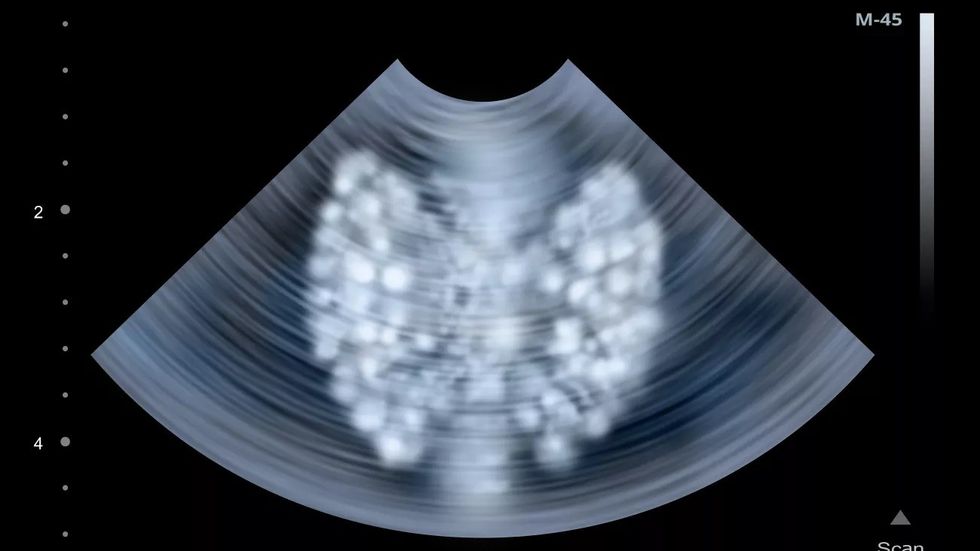

Format asimptomatike nganjëherë zbulohen rastësisht me analizën e kalciumit i cili është më i lartë se normal; me ultrazë të qafës dhe scintigrafi të gjëndrës paratiroide.